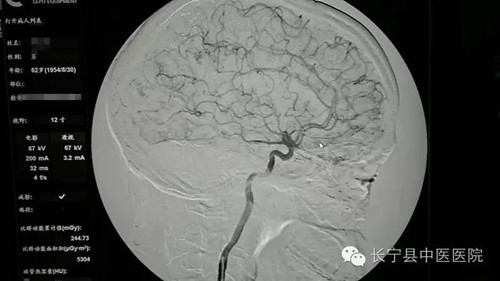

近日,我院外一科成功完成首例“全脑血管造影术”,这也是我县地区的首例,标志着我院外一科在血管造影技术方面又迈上一个新台阶。该手术的顺利实施,为我县及周边地区心脑血管疾病的患者带来了福音。

今年62岁的因外伤后右侧肢体乏力伴活动障碍2-月来我院就诊,平素常有头晕痛症状,经牵引、针灸、理疗等保守治疗效果不佳。 结合患者既往有脑梗塞病史、通过保守治疗效果不佳,可能会出现脑梗塞面积增多、偏瘫加重、甚至危及生命,我院外一科在李华桥副院长的带领下,科室团队经过认真研究,由雷明主任亲自主刀,决定对患者实施经股动脉穿刺行“全脑血管造影术”。该手术是一种微创手术,是指在局麻下,在高清摄像系统的监视下, 行“全脑血管造影术”并及时处理患者血管中的斑块本次手术完成了对左侧颈内动脉完全闭塞,靠椎动脉和对侧代偿供血,使偏瘫的患者竟然完全恢复了。与传统手术相比,该微创手术更加了解血管内的狭窄及血管内的斑块情况,具有创口小、损伤小、术后恢复快、住院时间短、费用低等优点。